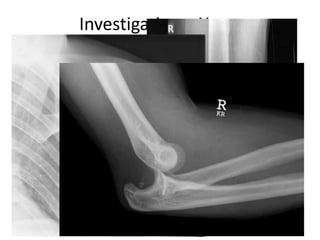

Investigations- Xrays

Dislocation

• No joint is immune from dislocation

• Most commonly occur in the following joints.